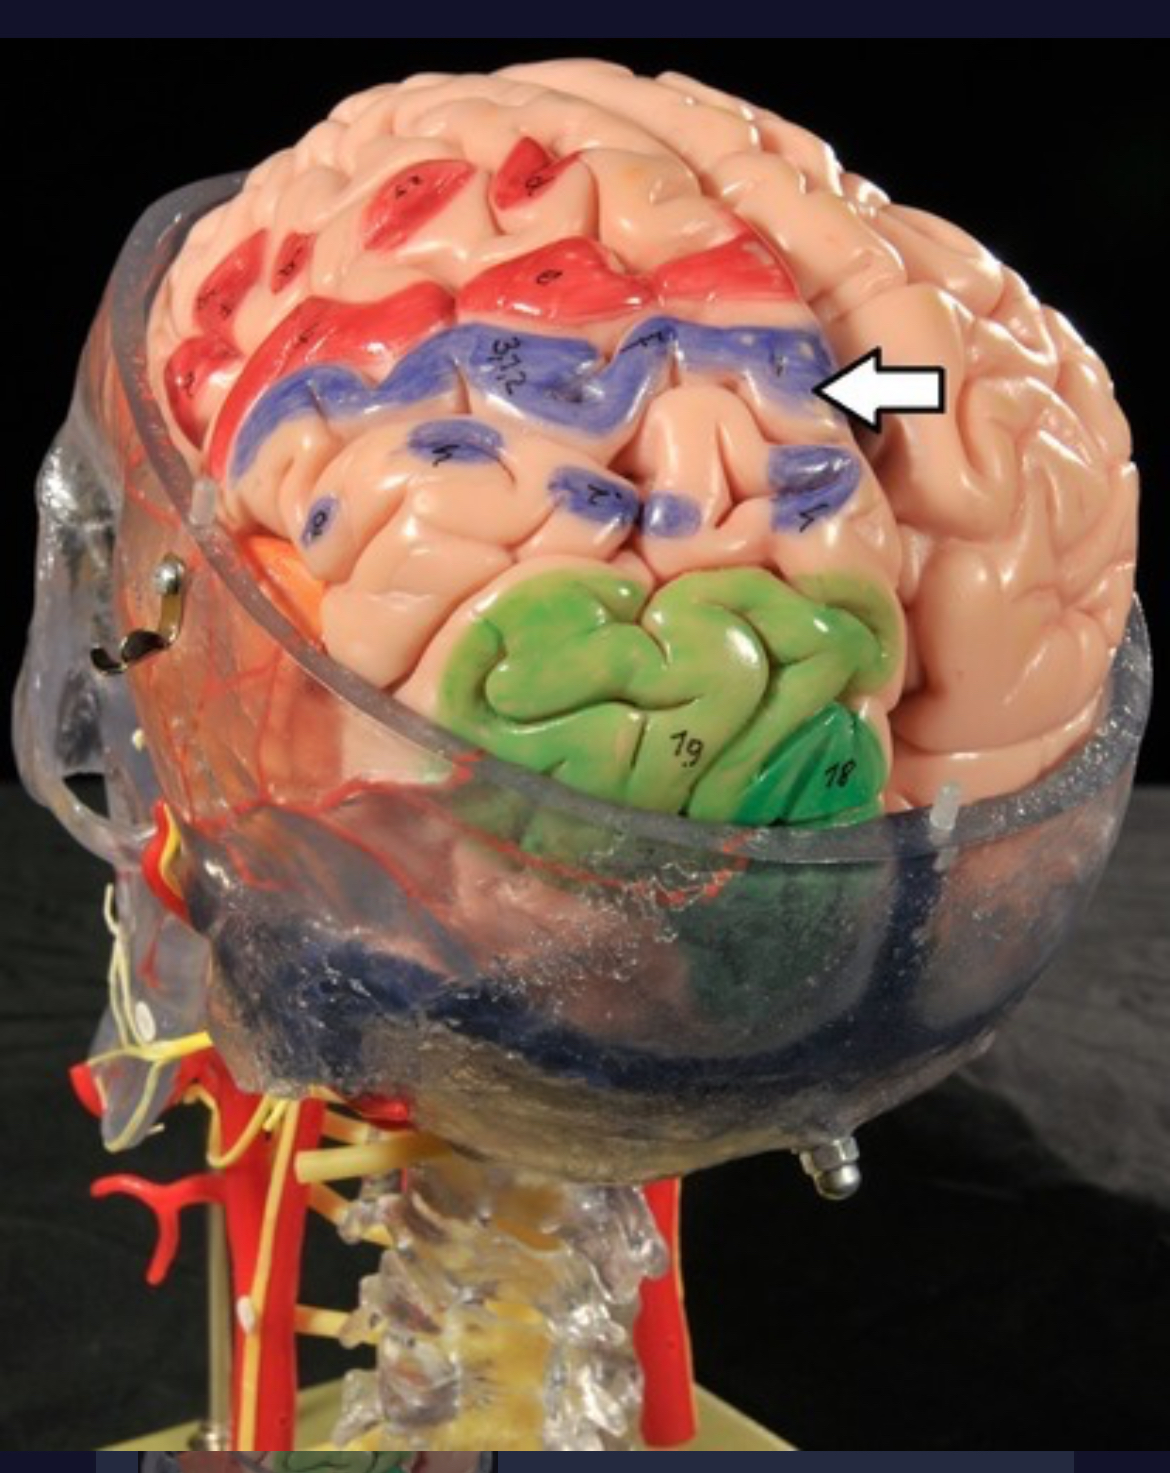

Precentral gyrus

Postcentral gyrus

Central sulcus